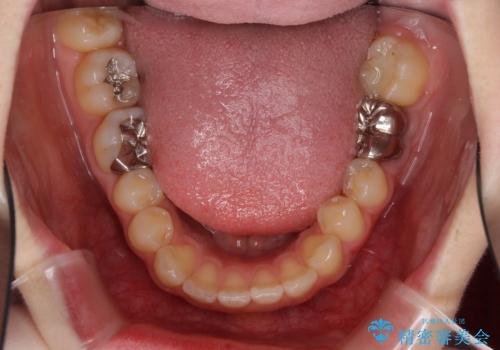

- 口の閉じにくさと割れてしまった奥歯を気にして来院された患者様です。

IPR(歯と歯の間を削る)と歯列全体の後方移動によって口元が引っ込むように設計し、インビザラインにより治療を行うこととしました。

割れてしまった奥歯は抜歯し、矯正治療中の良いタイミングでインプラントを埋入することとしました。

インプラントは、治療期間を短くすることが可能な、ストローマン社のSLActiveを使用することとしました。

上下正中がずれていたため、抜歯による矯正治療も検討しましたが、口元がそれほど突出していなかったため、非抜歯にて矯正することになりました。

その結果正中のズレは残りましたが、口を閉じたときの感覚や奥歯の咬み合わせには全く問題なく、患者様には大変満足していただきました。